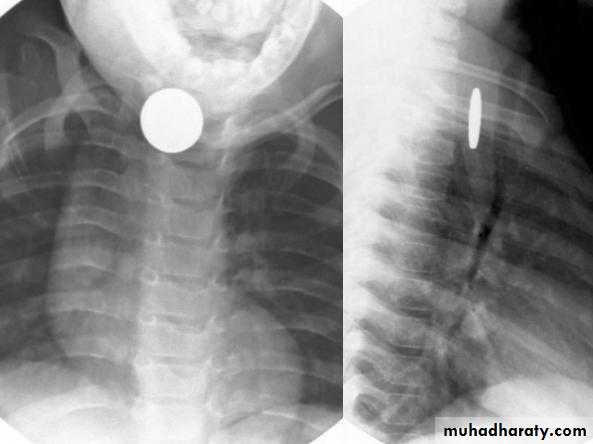

Chest X-ray:

DDx: FB in the esophagus